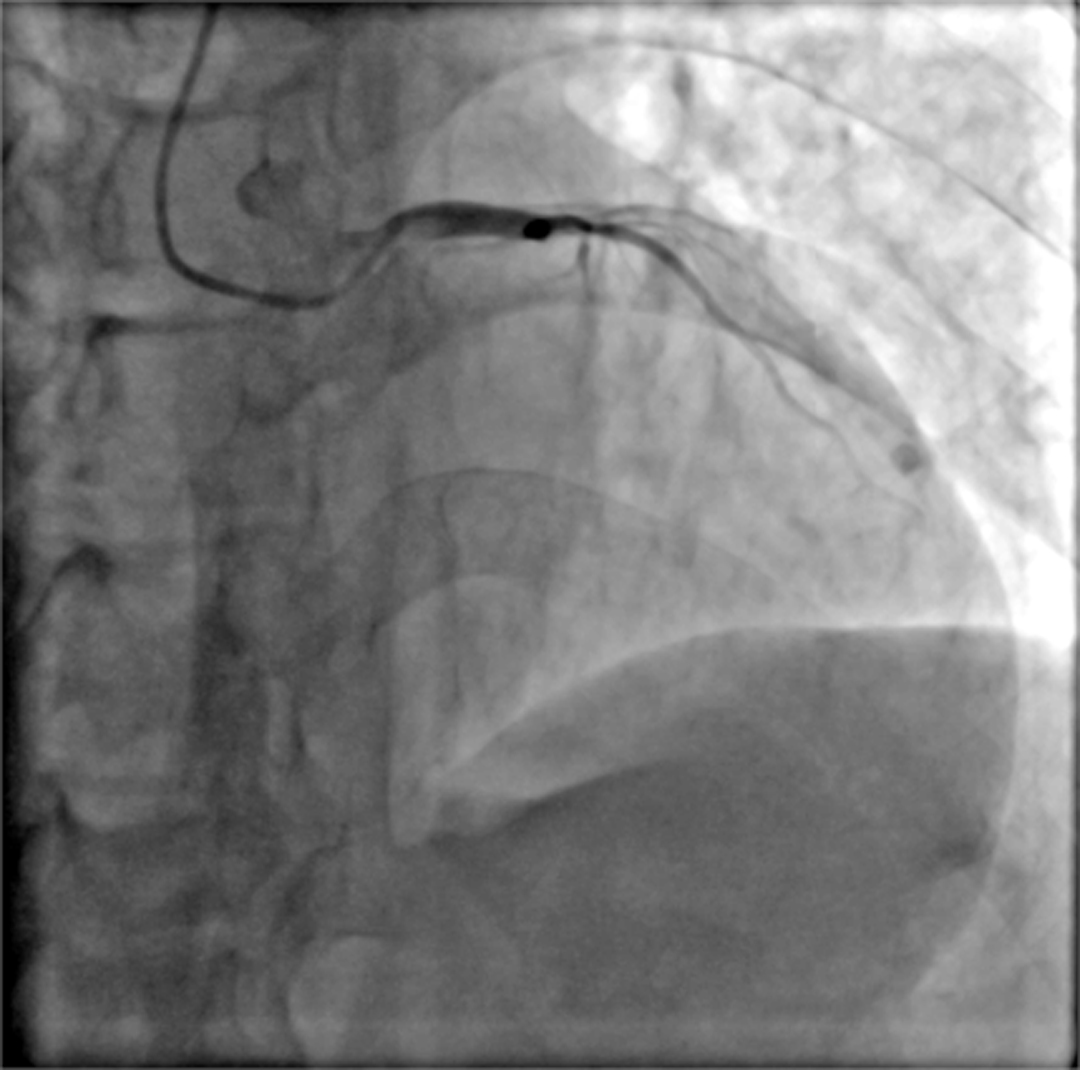

15:03,冠脉造影提示LAD近段闭塞,准备介入开通闭塞血管

术前